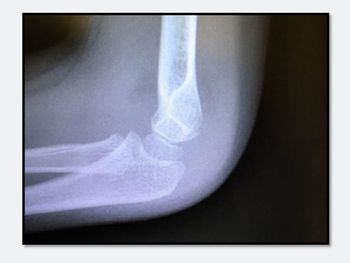

What type of injury is seen on this x-ray of a young boy's elbow? Outward signs of trauma are negligible.

The answer, and the evidence behind it, are essential knowledge for primary care.